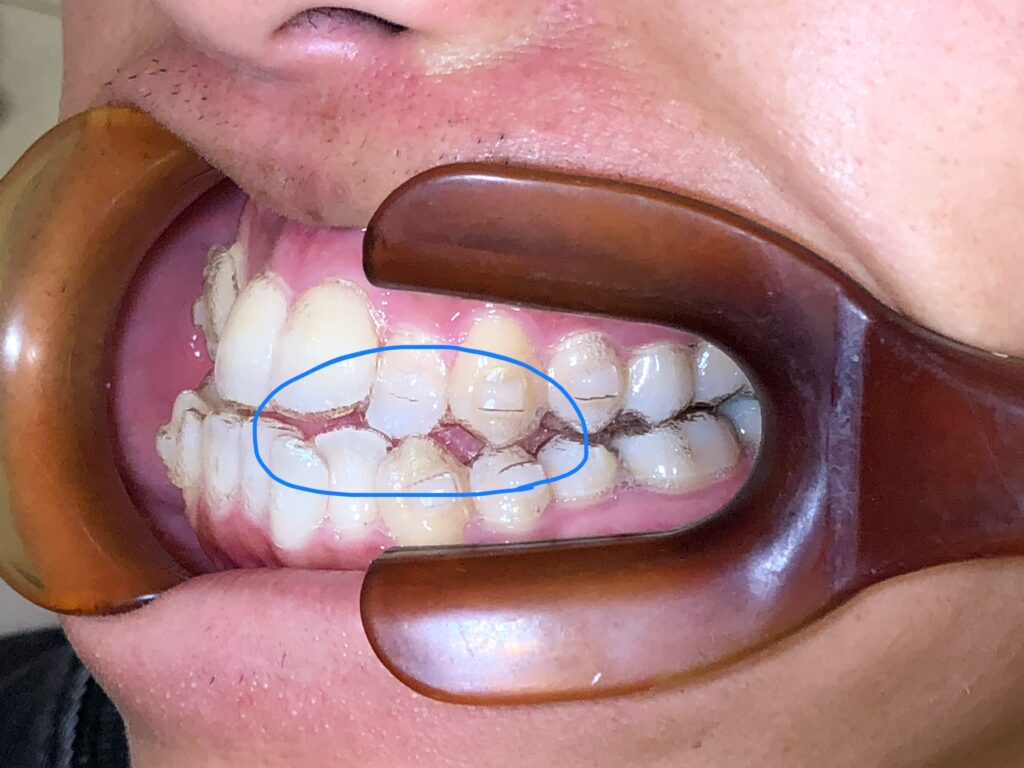

歯列矯正を終え、美しく整った歯並びを手に入れた後、多くの方が安心してしまいがちなポイントがあります。それが 「リテーナー(保定装置)の装着習慣」 です。

矯正後の歯は、表から見える以上に不安定です。歯が新しい位置で骨に固定されるまでには「数年単位」の時間が必要で、特に矯正装置を外した直後は、リテーナーなしでは簡単に元の方向へ動いてしまいます。

● 1カ月放置 → 明らかに歯並びが変わることも

特に前歯のねじれは戻りやすく、元の状態に近づいてしまうことがあります。

・もともとの歯並びが強いガタガタだった

捻転(ねじれ)が大きい歯ほど、戻ろうとする力が強いです。